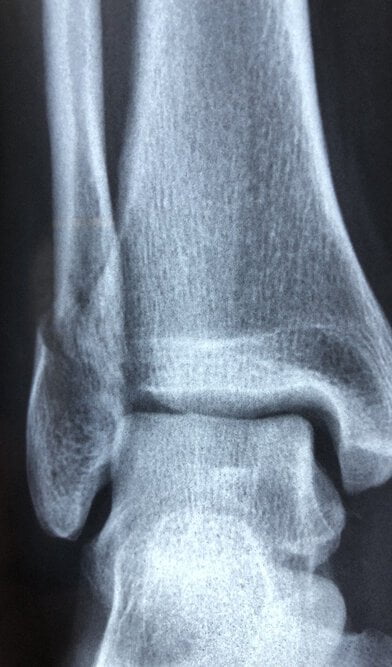

Osteoporose ist eine Erkrankung, bei der die Knochen schwinden und es leichter zu Brüchen kommen kann.

Osteoporose ist eine schleichende Erkrankung, da sie sich über viele Jahre hinweg entwickeln kann und meistens keine Symptome auftreten, bis es zu einer Fraktur kommt. In einigen Fällen werden die Knochen so brüchig, dass sie sogar bei einem leichten Sturz, beim Husten oder Niesen brechen können.